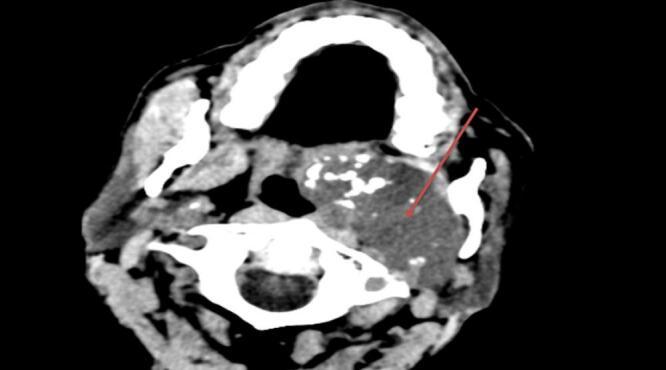

Here we present a 60 years old male patient presented with foul smelling nasal discharge, nasal obstruction and snoring of 2 years duration and Head CT scan was concluded to be advanced nasopharyngeal carcinoma but histopathology result turned out to be the uncommon nasopharyngeal chordoma. Therefore, he was treated with surgical excision and adjuvant radiotherapy.

我们在此呈现一名60岁男性患者,有2年的恶臭鼻涕、鼻塞和打鼾症状,头部CT扫描诊断为晚期鼻咽癌,但组织病理学结果显示为罕见的鼻咽部脊索瘤。因此,他接受了手术切除及辅助放疗。